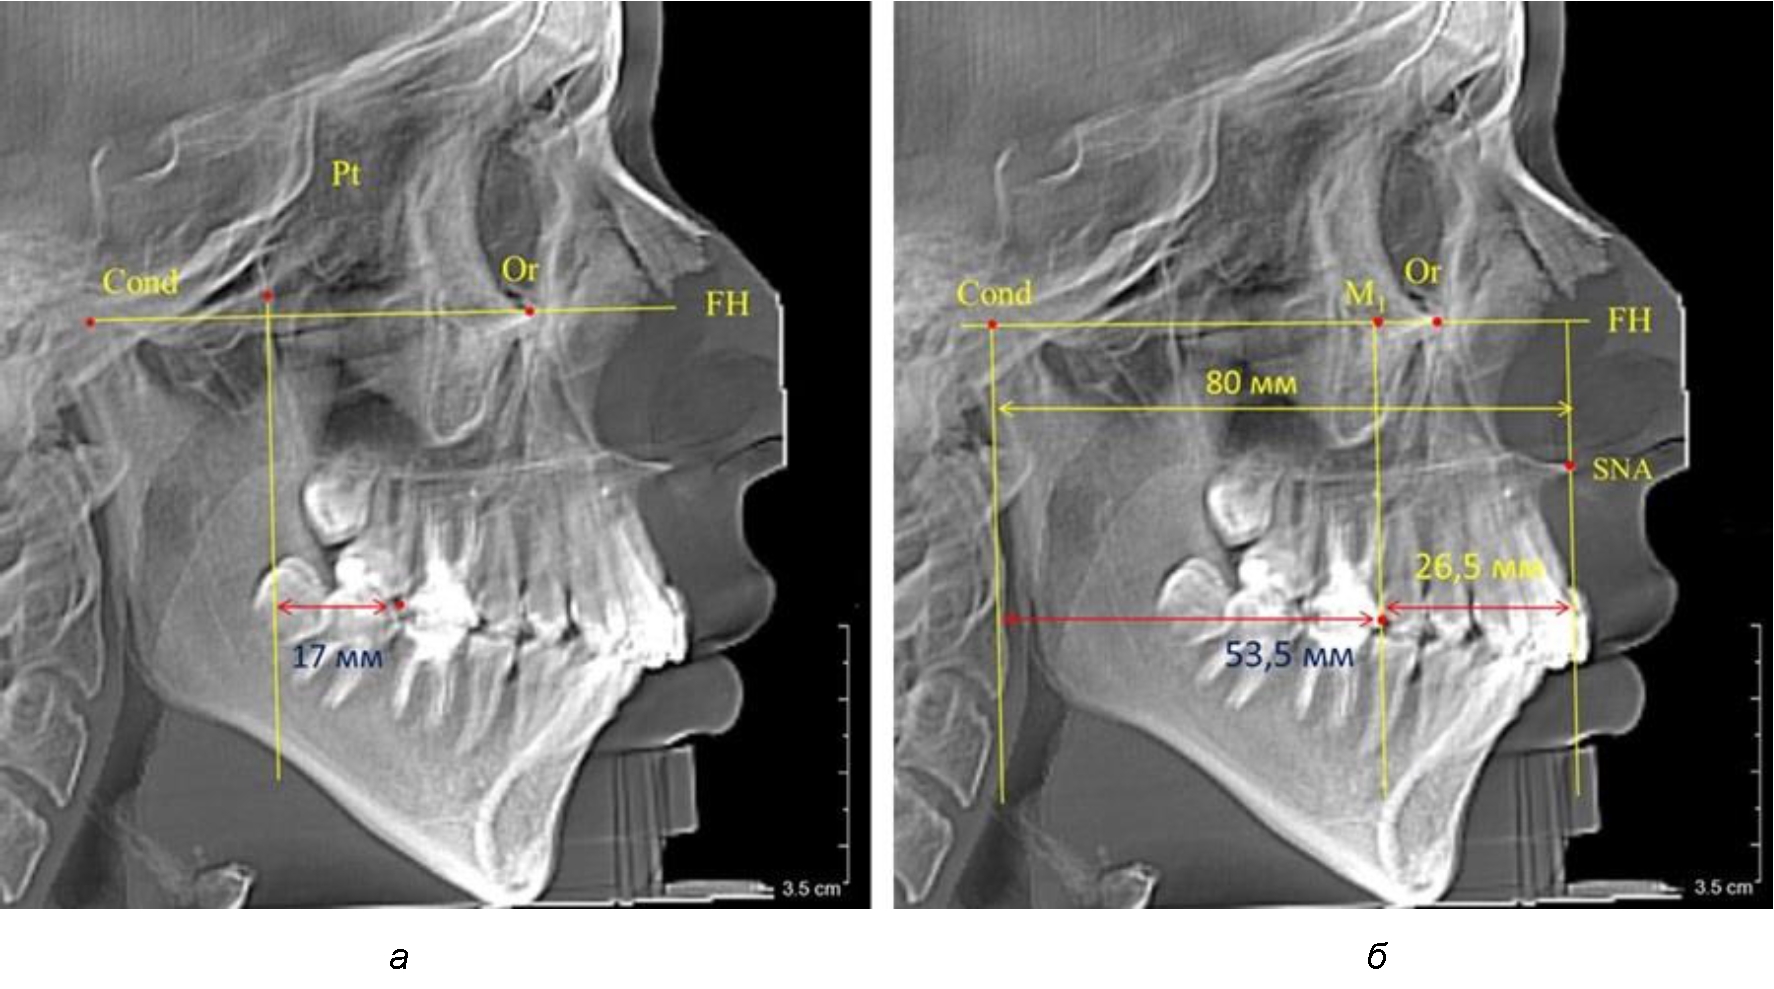

При проведении анализа к Франкфуртской горизонтали проводили передний и задний перпендикуляры. Передний спинальный перпендикуляр проходил через выступающую точку передней носовой ости (spina nasalis anterior – SNA), а задний суставной перпендикуляр опускали из кондилярной точки Cond. Молярный перпендикуляр проводили через медиальную поверхность первого постоянного моляра. Указанная вертикаль отделяла замещающие зубы постоянного прикуса от добавочных зубов (постоянных моляров), что вполне логично для анализа положения первых постоянных моляров в гнатическом комплексе (рис. 1).

Рис. 1. Метод определения положения первых верхних моляров по Ralph E. McDonald (а) и по предложенному методу (б)

Так, при расстоянии от крыловидной вертикальной плоскости PTV до дистальной поверхности верхнего первого постоянного моляра в 13 мм сагиттальный размер гнатического отдела был 82 мм. При этом отношение кондилярно-спинального расстояния к кондилярно-молярному размеру (54,5) было близким к коэффициенту 1,5, что представлено на рис. 2.

Рис. 2. Особенности положения первых моляров по R. E. McDonald (а) и по предложенному методу (б) при уменьшенном молярно-крыловидном расстоянии